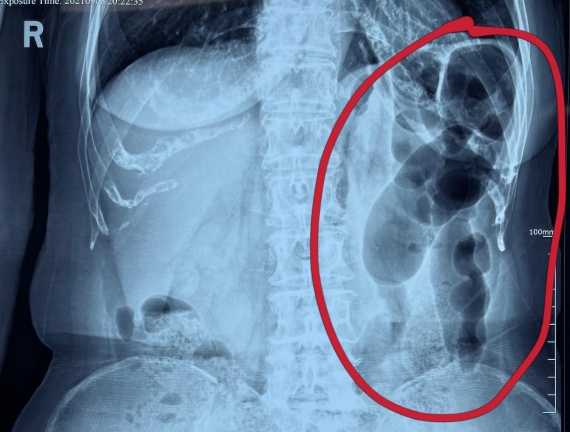

據(jù)省醫(yī)院消化病院消化二科姜子曄醫(yī)生介紹,韓大娘今年已經(jīng)73歲,家住哈爾濱市,一周前開(kāi)始腹脹腹痛,有較為明顯的左側(cè)腹部疼痛,疼痛劇烈時(shí)會(huì)出現(xiàn)左側(cè)腹部鼓包情況,排氣排便后有所好轉(zhuǎn)。韓大娘家人見(jiàn)狀將其送到了黑龍江省醫(yī)院,門(mén)診檢查腹部平片提示為左側(cè)腹部積氣,口服全消化動(dòng)力藥及通便治療后腹痛腹脹有所緩解,入院前再次突發(fā)左側(cè)腹痛加重伴有明顯腹脹,急診隨后以“腹痛腹脹原因待查”將韓大娘收入到消化病院消化二科。

姜子曄醫(yī)生熱情接待了韓大娘,為其進(jìn)行了仔細(xì)查體,除了左側(cè)腹部壓痛并未見(jiàn)明顯異常,對(duì)癥給予灌腸后,韓大娘的腹脹有所緩解,第二天姜子曄醫(yī)生為韓女士進(jìn)行了胃腸鏡檢查,也未見(jiàn)明顯異常。但此時(shí)韓大娘腹部平片結(jié)腸腸管擴(kuò)張仍然很?chē)?yán)重,腹痛腹痛也沒(méi)緩解,到底什么原因呢?消化二科主任陸以霞在查房時(shí)建議繼續(xù)給予韓大娘口服全消化動(dòng)力藥,必要時(shí)灌腸治療,同時(shí)陸以霞主任在追問(wèn)病史查體時(shí)發(fā)現(xiàn)韓大娘左下腹紅色皮疹和小水泡,反復(fù)抓撓腹部皮膚部分已結(jié)痂,高度懷疑為帶狀皰疹。